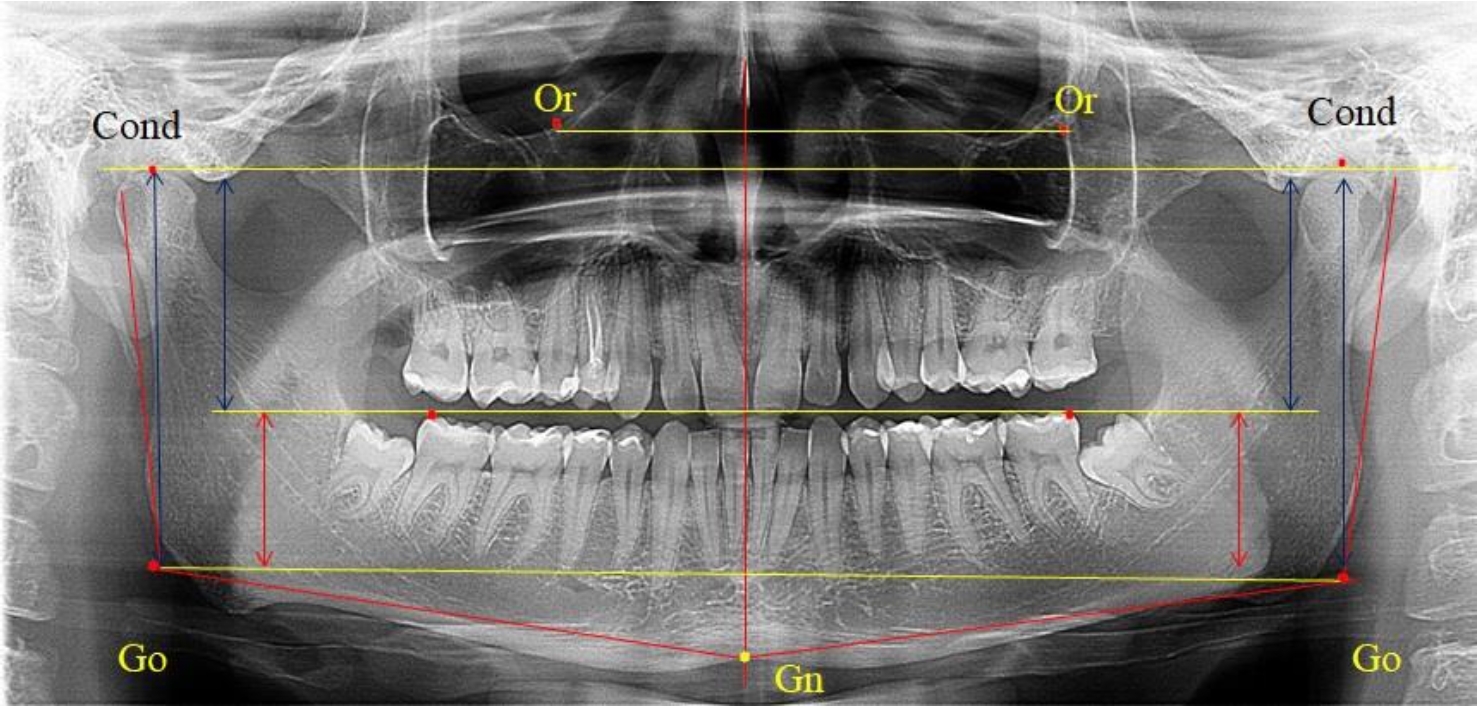

В 1-ю подгруппу были включены 36 комплектов телерентгенограмм и ортопантомограмм [или (48,65 ± 5,81) % от общего количества], на которых средняя величина отношения верхней части ветви к нижней составляла 1,95 ± 0,03, что соответствовало показателям, полученным по группе в среднем, но с меньшим показателем ошибки среднего значения. Визуально верхняя окклюзионно-суставная часть выглядела вдвое больше нижней окклюзионно-гониональной (рис. 2). При этом высота ветви составляла (62,09 ± 1,22) мм. Максимальная высота была 71 мм, а минимальная – 55 мм. Высота верхней части составляла (41,02 ± 0,77) мм, а высота нижнего отдела ветви была (21,09 ± 0,51) мм.

Рис. 2. ОПТГ пациента 1-й группы с оптимальным коэффициентом соотношения частей ветви нижней челюсти